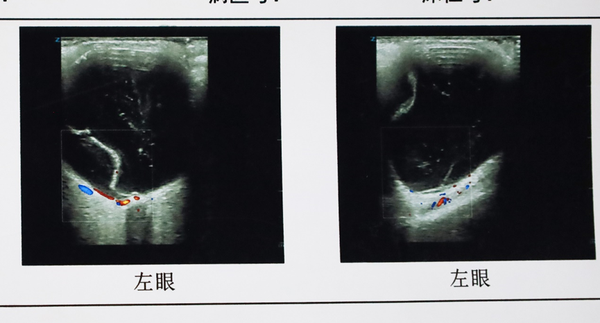

经李院长详细检查,张女士存在“左眼孔源性视网膜脱离”。更麻烦的是脱离网膜已波及黄斑区,导致视力急剧下降,仅剩手动/30cm,和失明无样,走路需要人扶。

面对张女士复杂而紧急的病情,李玉军教授与眼底病科孙利娜主任等骨干成员认真研究检查结果,给出了有针对性的解决方案——微创玻璃体切割手术联合视网膜复位。

由于张女士1200度的近视,眼轴较普通人长很多,而且球壁(即巩膜和脉络膜)变薄、变性,手术中要克服器械长度,视网膜复位等重点问题。

在显微镜下,李玉军娴熟地切除混浊玻璃体,剥离并切除玻璃体后界膜就网膜前薄层膜状物,切除裂孔处粘连牵拉的玻璃体,松解裂孔及变性区的牵引......‘精细’二字在此被展现的淋漓尽致。

在40分钟左右时间,张女士的手术顺利完成。术后经过一段时间的精心休养和康复,张女士左眼的视网膜复位良好,已经可以看到0.25了,这对1200度近视的视网膜脱离患者显得难能可贵。